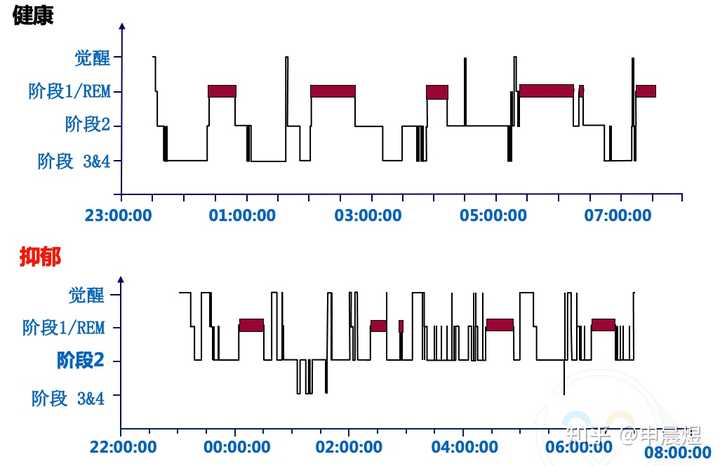

抑郁症患者的睡眠结构节律紊乱[8]